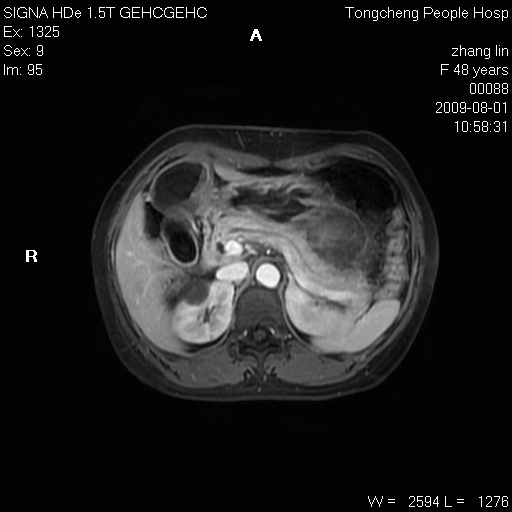

女,48岁。健康体检,彩超发现右肾占位性病变。平素健康。

临床诊断:右肾占位性病变,性质待定(囊肿?肿瘤?)。

上中腹部mr平扫+增强扫描,图像如下:

右肾上极见一类圆形病灶,t1wi呈等信号t2wi呈等高混杂信号,三期增强无强化,边界清---考虑囊肿出血。

同反相位均表现为等信号,病变无强化,考虑含蛋白的囊肿可能,弥散加权相或许有些帮助,